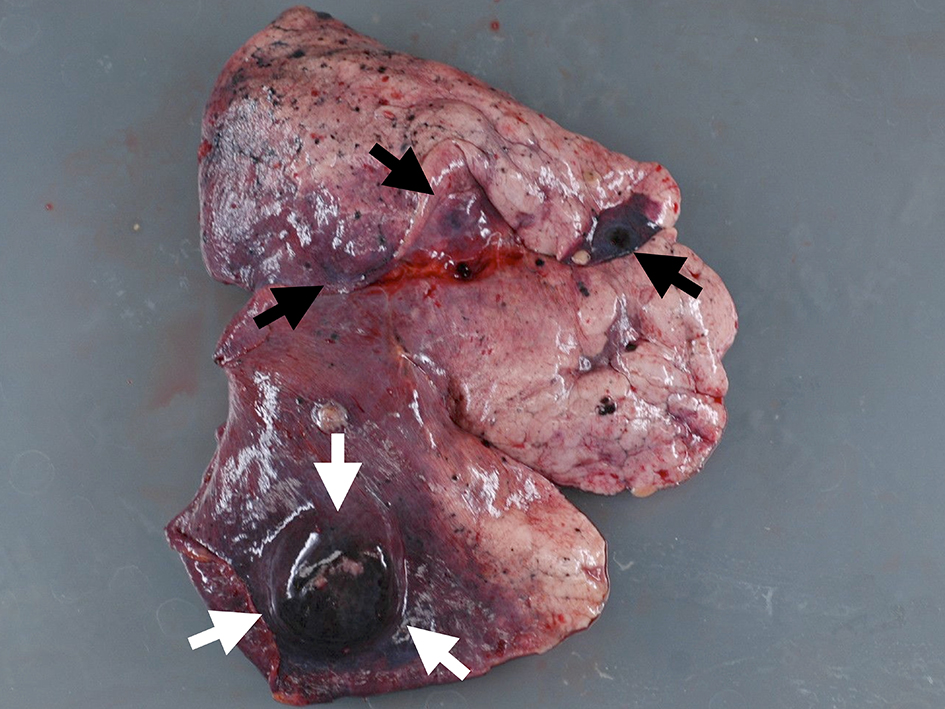

The autopsy reported a blackish swollen liver, 3,600 g in weight (Fig. 4), disseminated blackish tumors of the bilateral lungs (Fig. 5) and widely spread metastatic lesions in the vertebrae (Fig. 6), ribs and lymph nodes in the abdominal and thoracic cavity as well as the mediastinum, submucosa of the stomach and spleen. Massive tumor cell emboli were observed in the main trunk of the portal vein and its branches within a wide area, including the epigastric vessels.

![]() Click for large image | Figure 4. Macroscopic view of liver cut surface. Blackish swelled liver showed diffuse metastatic melanocyte invasion (arrows). |

![]() Click for large image | Figure 5. Macroscopic view of lung lesion. Well-defined metastasis (white arrows) was accompanied with multiple metastases (black arrows). |